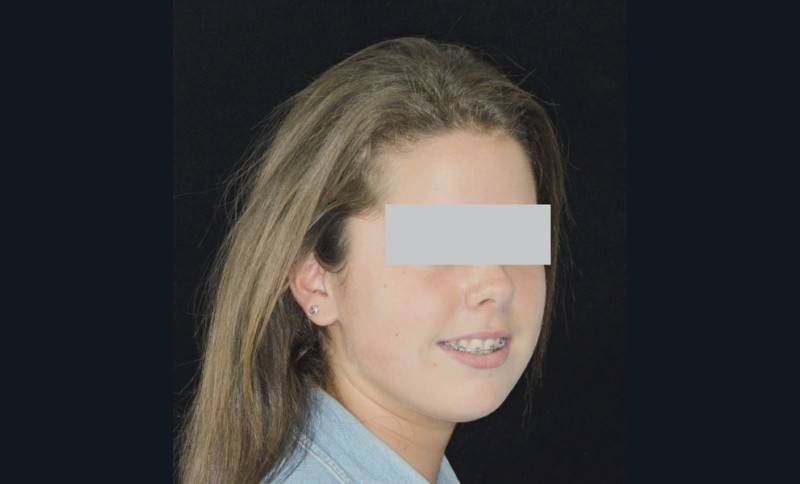

Camille âgée de 12 ans et 7 mois se présente à la consultation adressée par son chirurgien-dentiste.

Son profil convexe s’inscrit dans un contexte de rétrognathie hyperdivergente associée à une proalvéolie et un encombrement maxillo-mandibulaire.